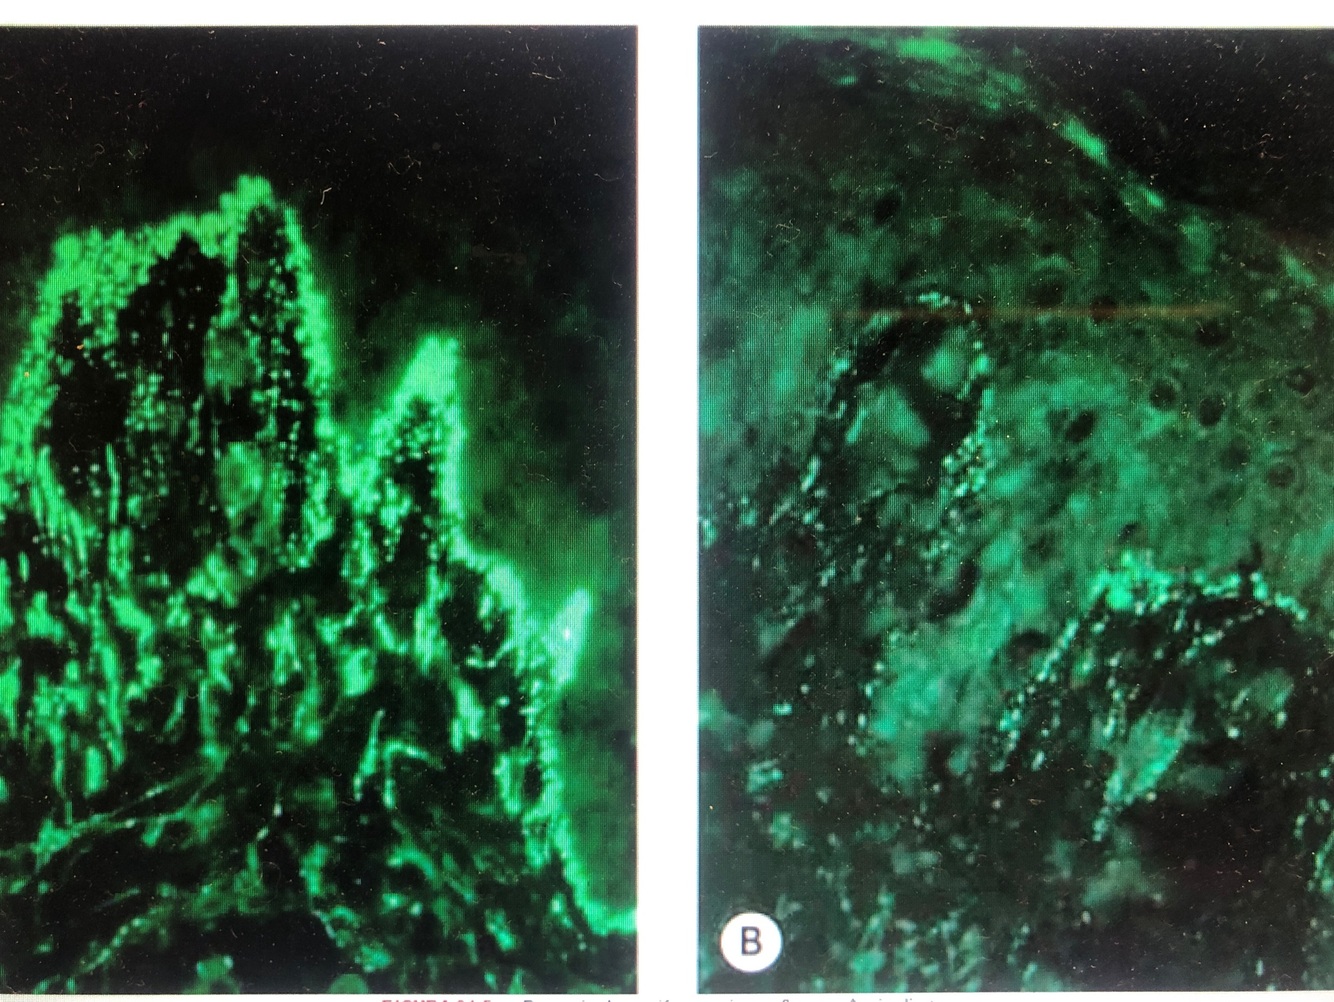

Qual o dx?

Penfigoide bolhoso

Ap: clivagem subepidermica, com neutrofilos e eosinofilos

Salt split skin: fluorescencia no teto da bolha